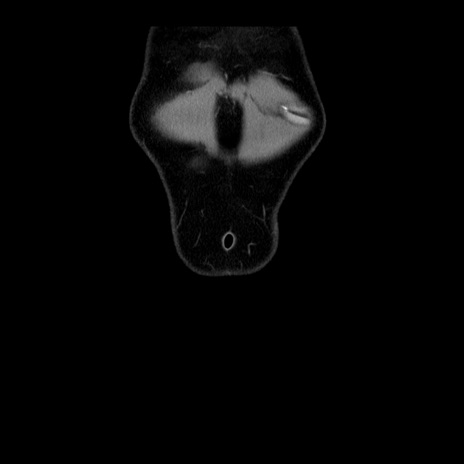

症例4(冠状断像)

横断像